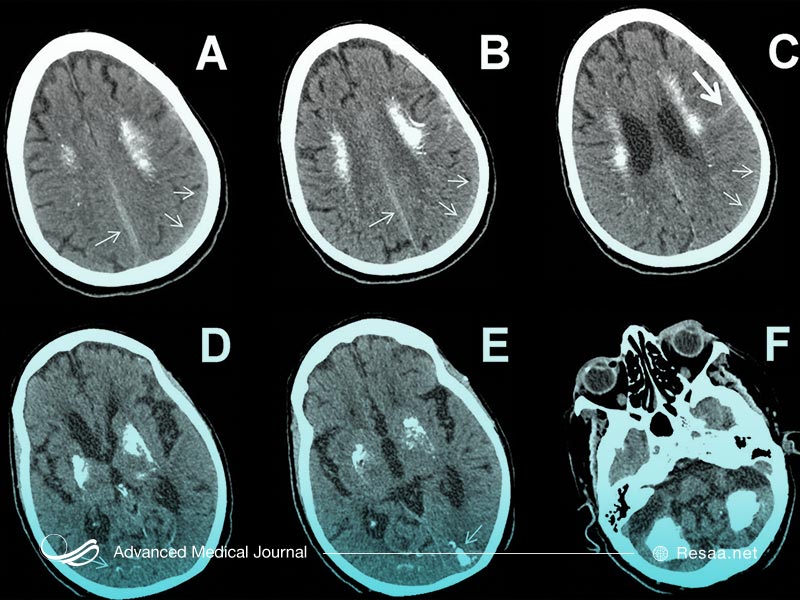

کلسیفیکاسیون مغز

کلسیفیکاسیون اولیه ارثی مغز زمانی اتفاق میافتد که رسوبات غیرطبیعی کلسیم در رگهای خونی مغز تشکیل شوند. به طور معمول این رسوبات در گانگلیونهای “ganglia” پایه شکل میگیرند که حرکت بدنی را آغاز و کنترل مینمایند.

مانند بسیاری از انواع دیگر کلسیفیکاسیون، رسوبات کلسیم تنها با استفاده از اسکن تصویربرداری قابل مشاهده خواهد بود.